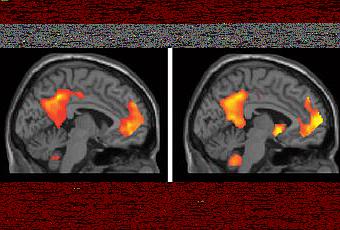

A gauche le sujet pense au passé, à droite à l’avenir. Ou le contraire, je ne sais plus …

Le résultat IRM est amusant, mais signifie quelque chose pas du point de vue du temps, mais de celui de la biologie. En premier lieu, je rappellerai que le cerveau est un objet tridimentionnel, et en n’en montrant qu’une coupe, on ne voit en fait rien, ou pas grand chose. Donc, les techniques d’imagerie mises en place permettent de localiser des zones précises du cerveau, selon un point de vue assez réductionniste. Je remarque enfin qu’il n’y a pas d’image correspondant au présent : si ces zones étaient allumées lorsque le sujet pense à des événements se passant dans le présent, le passé ET le futur, cette expérience ne signifierait alors rien du tout : ces zones s’allument tout le temps quand on pense, point. Il semble donc y avoir un biais dans l’expérience.